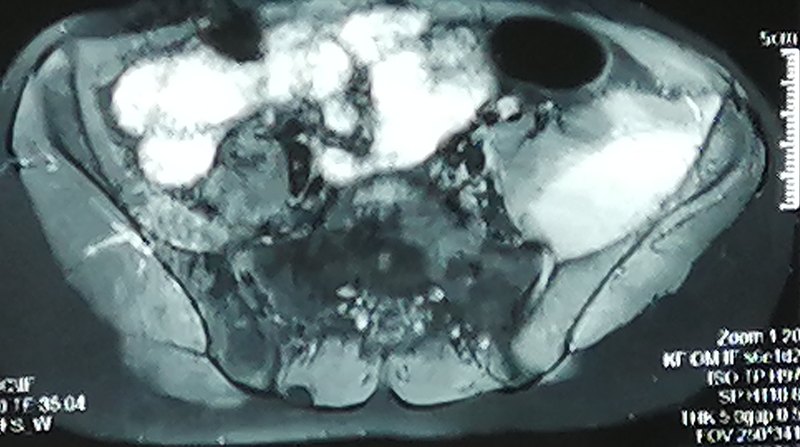

髂窝脓肿

髂窝是后腹膜与髂骨之间的间隙。髂窝脓肿,多因金葡菌,链球菌,大肠杆菌经血行或淋巴感染引起。 表现:起病急,发烧,寒战,乏力,恶心,呕吐,患侧腹股沟皮肤红肿疼痛,同侧髋关节活动受限,伸髋疼痛加剧,行走困难。Tomas征阳性。 检查: 1、血像,C反应蛋白,血沉增高。 2、局部穿刺细菌培养阳性。 3、彩超,MRI提示髂窝包块。 4、需做结核抗体,胸腰椎MRI除外胸腰椎结核流注型脓肿。 治疗: 1、一般治疗,卧养,加强营养,脓肿液化不明显时采用局部热敷,理疗。 2、抗生素治疗。 3、手术治疗,切开引流术。手术时注意避免污染腹腔,避免术中损伤股动静脉股神经。沿腹股沟韧带内侧切口不超过腹股沟韧带中线。